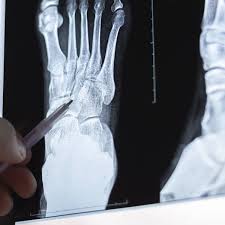

Lo más inquietante es que estas alteraciones no se limitan a animales de laboratorio. Los investigadores lograron identificar en humanos partículas plásticas en cartílago, discos intervertebrales y médula ósea, con concentraciones que alcanzan decenas de partículas por gramo de tejido óseo. Estas partículas provocan estrés oxidativo y alteran las señales de las células madre conduciendo a una pérdida progresiva de la capacidad regenerativa del esqueleto humano.

La osteoporosis es una enfermedad que debilita los huesos y aumenta el riesgo de fracturas. Afecta especialmente a mujeres posmenopáusicas y personas mayores. Según la Fundación Internacional de Osteoporosis (IOF), se espera que las fracturas relacionadas con esta enfermedad aumenten un 32% para 2050 debido al envejecimiento de la población.